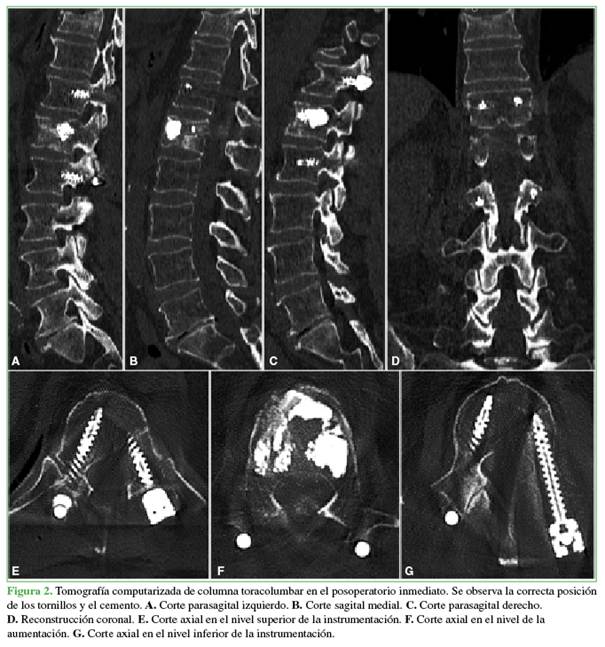

Imágenes preoperatorias

En la Figura 1, se muestran las imágenes de resonancia magnética de columna lumbar, con cortes sagitales, de las secuencias T1, T2 y STIR, así como un corte axial sobre el cuerpo vertebral de L1. Se observa una lesión que compromete la estructura del cuerpo vertebral e involucra la columna anterior en relación predominante con el segmento L1-L2, sin compromiso del canal vertebral, hipointensa en las secuencias T1/T2 e hiperintensa en la secuencia STIR.